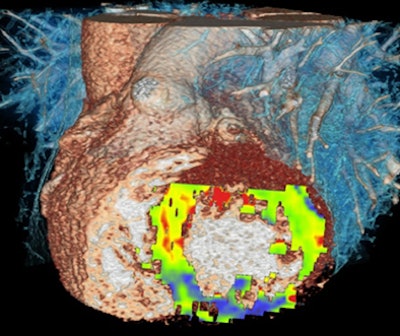

The following paragraphs describe three patients who underwent the comprehensive DSCT protocol along with SPECT myocardial perfusion and MRI for comparison. All images relate to the first patient.

| Images are of a 64-year-old man with a past history of inferolateral myocardial infarction. Rest coronary CT angiography revealed distal right coronary artery occlusion. Functional analysis during systole and diastole showed inferolateral akinesis. First-pass adenosine stress dynamic perfusion CT demonstrated inferior and inferoseptal perfusion defect, confirmed on MRI and SPECT. This perfusion defect corresponds to chronic infarction, as confirmed by delayed-enhancement CT and MRI. Images courtesy of Dr. Gorka Bastarrika, Ph.D. |